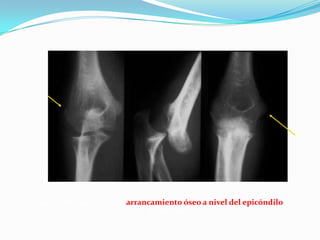

Avulsión del Epicóndilo

Luxación posterior con arrancamiento óseo a nivel del epicóndilo y la

epitróclea